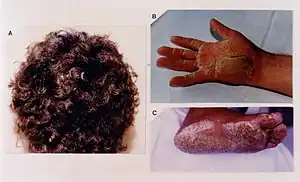

| Woolly hair and other symptoms of Naxos syndrome | |

The presence of woolly hair may indicate other problems such as with the heart in Naxos-Carvajal syndrome.[4] Diagnosis is suspected by its general appearance and confirmed by scanning electron microscopy.[5]

Woolly hair nevus is a localised area of wooly hair, which may occur on its own, or appear as dark twisted and kinking hair in an adult.[2] 50% of people with woolly hair nevus have a warty skin lesion on the same side of the body.[2] It may be associated with eye problems such as two different coloured eyes or strands of tissue across the pupil of the eye.[2] Other associations include ear problems, kidney disease, tooth decay, impairment of bone growth, and other skin lesions.[2]

Generalised woolly hair is typically seen in Naxos-Carvajal syndrome, Noonan syndrome, and cardiofaciocutaneous syndrome.[2][4]

Naxos-Carvajal syndrome

Familial woolly hair is autosomal recessive.[2] It may be part of a syndrome such as Naxos syndrome, due to passing on of mutations in the JUP gene.[4] When part of Carvajal syndrome, it is due the passing of mutations of the Desmoplakin gene.[4] The two syndromes caused by two different genes, are considered as one entity; Naxos-Carvajal syndrome.[4]